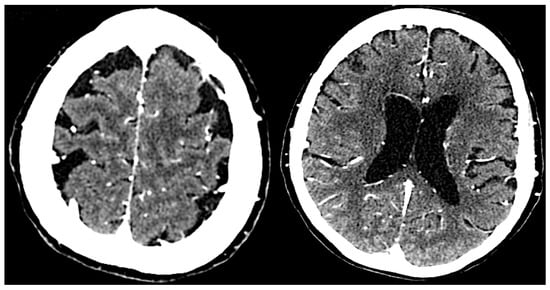

Neuroimaging supports the diagnosis by revealing structural changes in the brain associated with neurosyphilis (Figure 2). Magnetic Resonance Imaging (MRI) can show cortical atrophy, white matter lesions, and vascular abnormalities. Specific findings, such as hydrocephalus or lesions in the basal ganglia, can suggest neurosyphilis-related pathology [50,51,52]. Computed Tomography (CT) scans also identify significant structural abnormalities and rule out other causes of neurological symptoms, such as tumors or hemorrhages [52].

Figure 2.

The brain CT scan shows cerebral atrophy with slight ventricular enlargement.